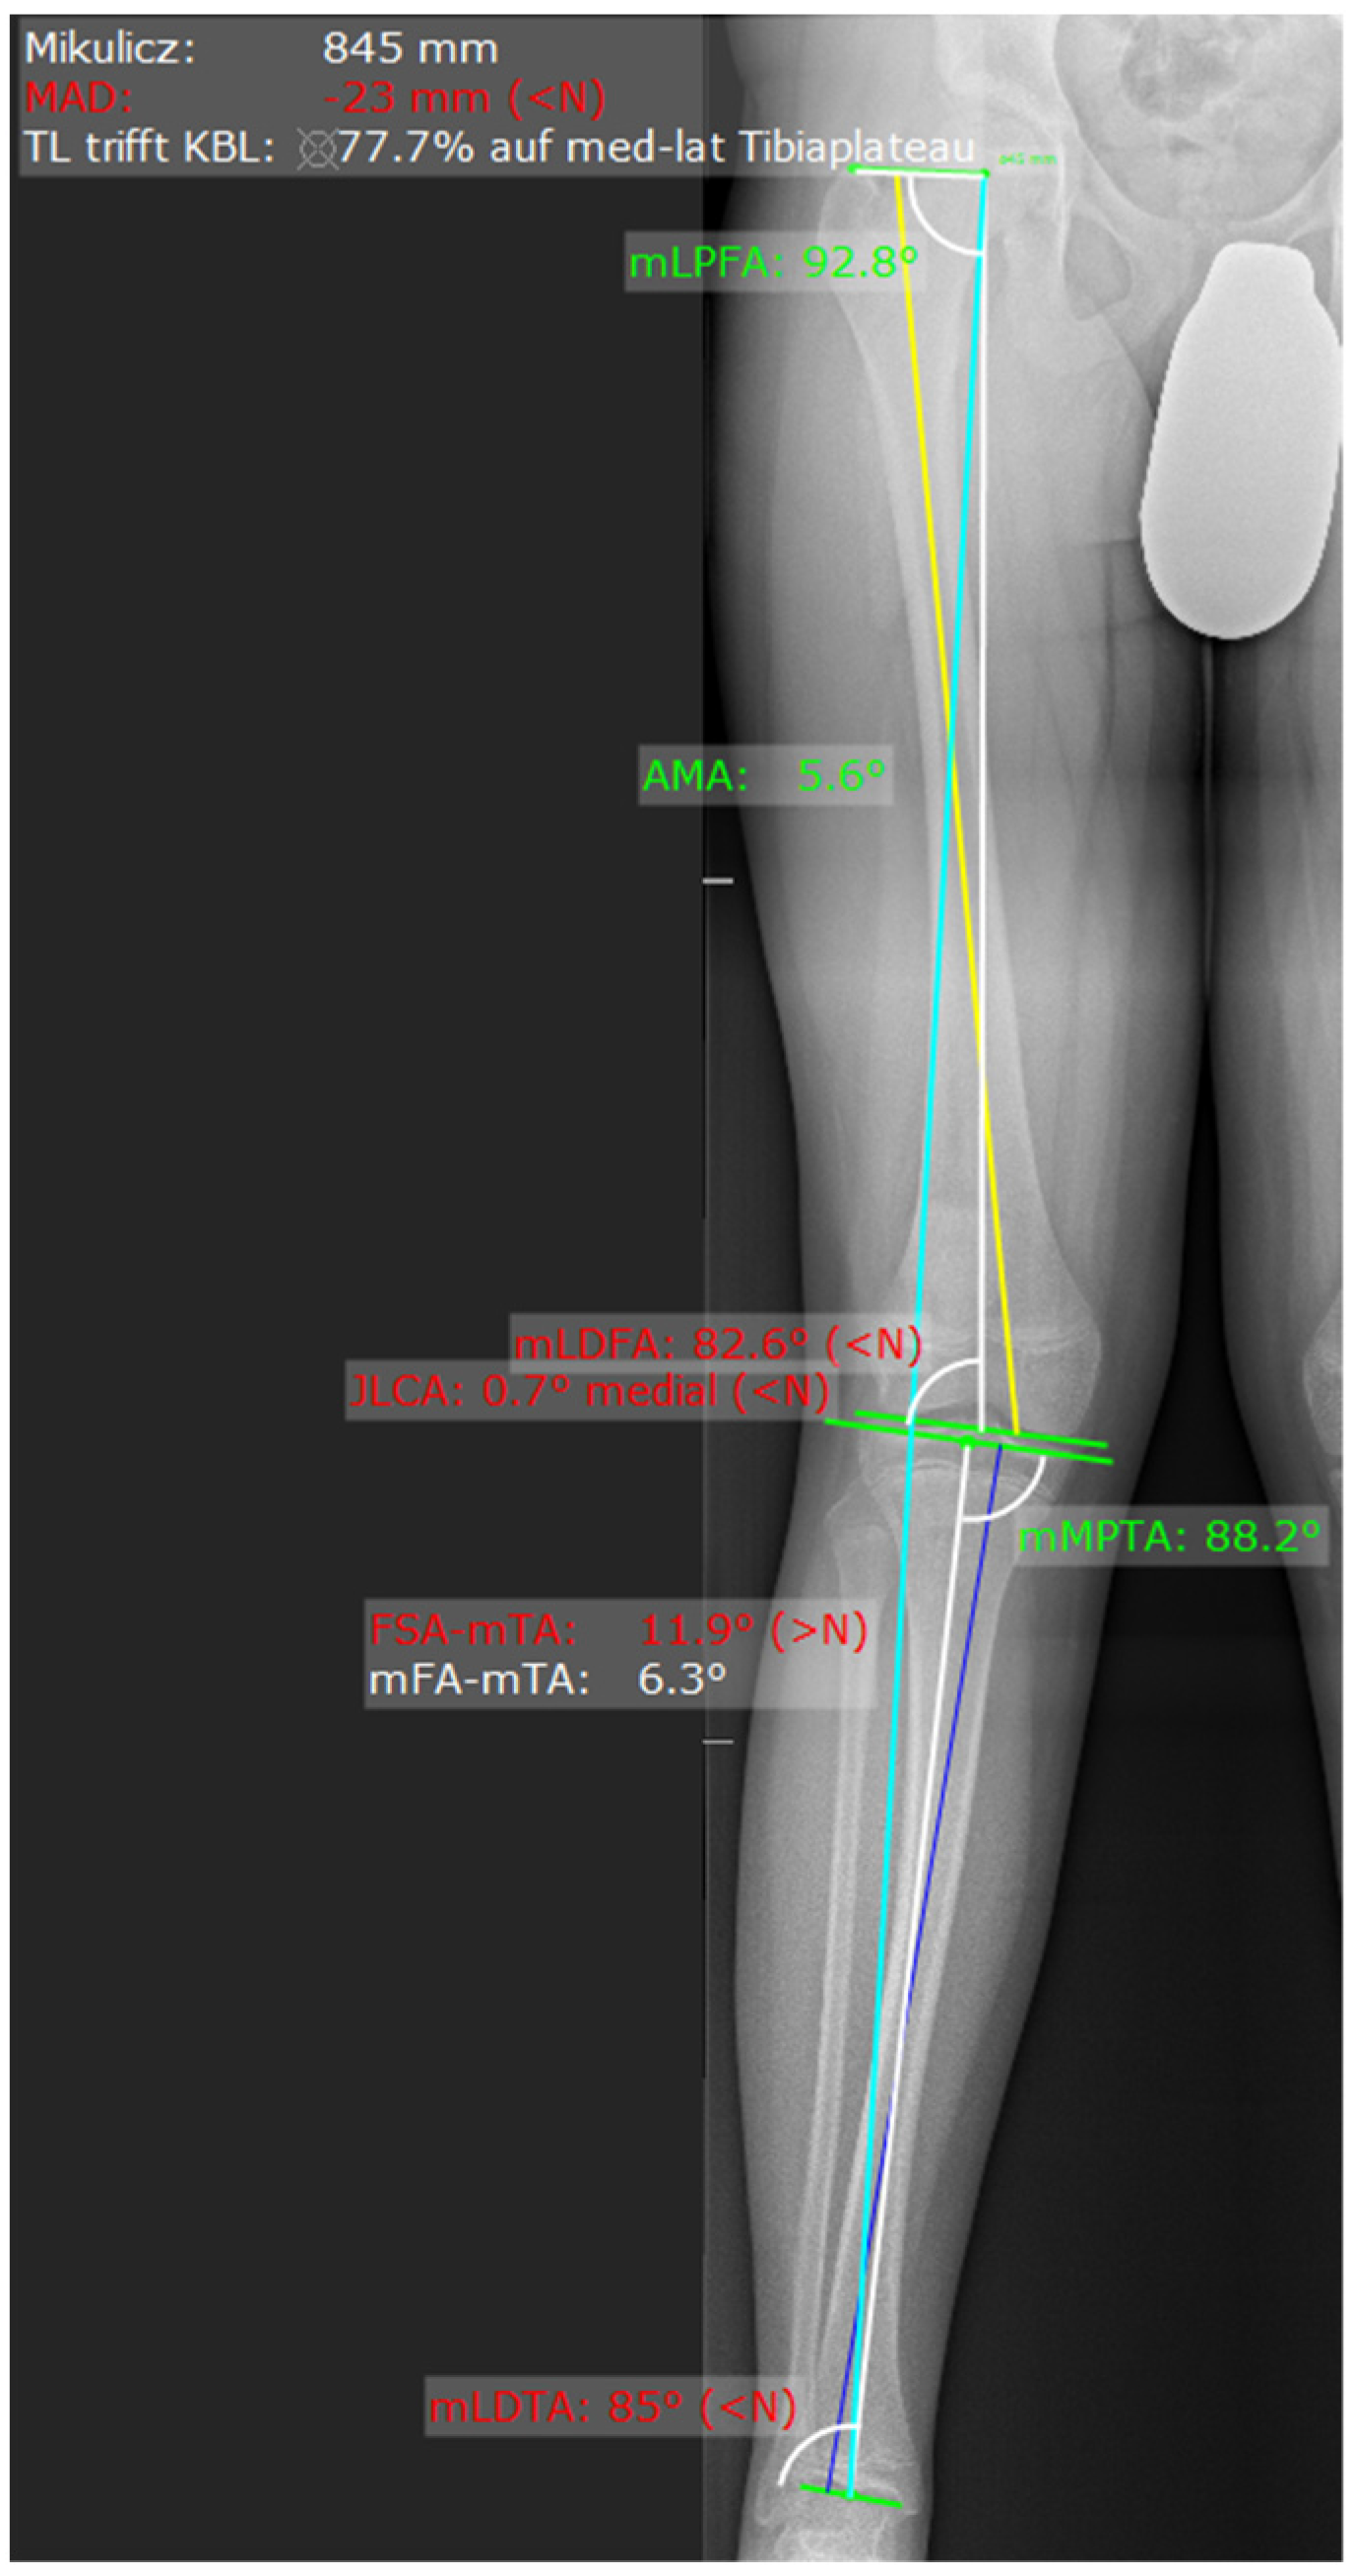

On the radiograph, the mechanical axis (Mikulicz line) was drawn from the center of the femoral head to the center of the talus, and the lateral and medial compartment of the knee joint was divided into three equal zones. If the mechanical axis intersected the middle third, a relative surgical indication was given; if it intersected the lateral or medial third, an absolute surgical indication was established (Figure 1). This technique and classification was described by Muller and Muller-Faber [14]. To determine whether the distal medial femur or the proximal medial tibia should be addressed, a deformity analysis was performed by measuring the mechanical lateral distal femoral angle (mLDFA) and the mechanical medial proximal tibial angle (mMPTA) (Figure 2). The location of the deformity was identified based on these measurements (Table 1). Radiographic measurements were performed independently by the attending orthopedic surgeon and a board-certified radiologist. The indication for surgery was based on the measurements obtained by the surgeon. For the purpose of this study, the reported values represent the mean of the measurements obtained by the surgeon and the radiologist.

Figure 2. Measurement via MediCAT. Blue line from the femoral head to the talus represents the Mikulicz line. The yellow line represents the axis of the femur and the dark blue line the axis of the tibia.